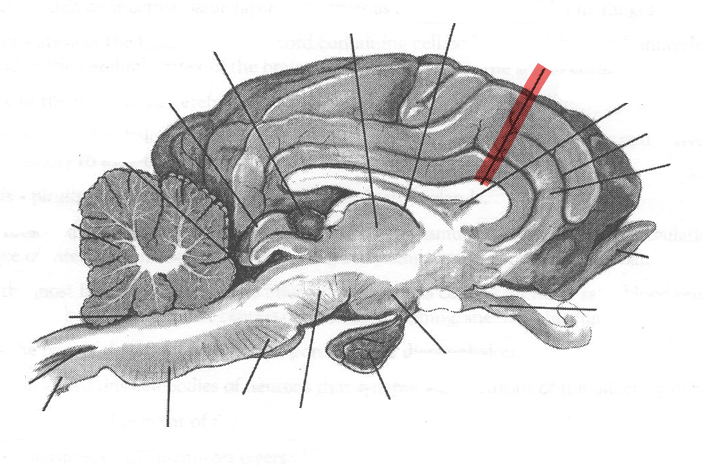

Identify highlighted arrow

Medulla